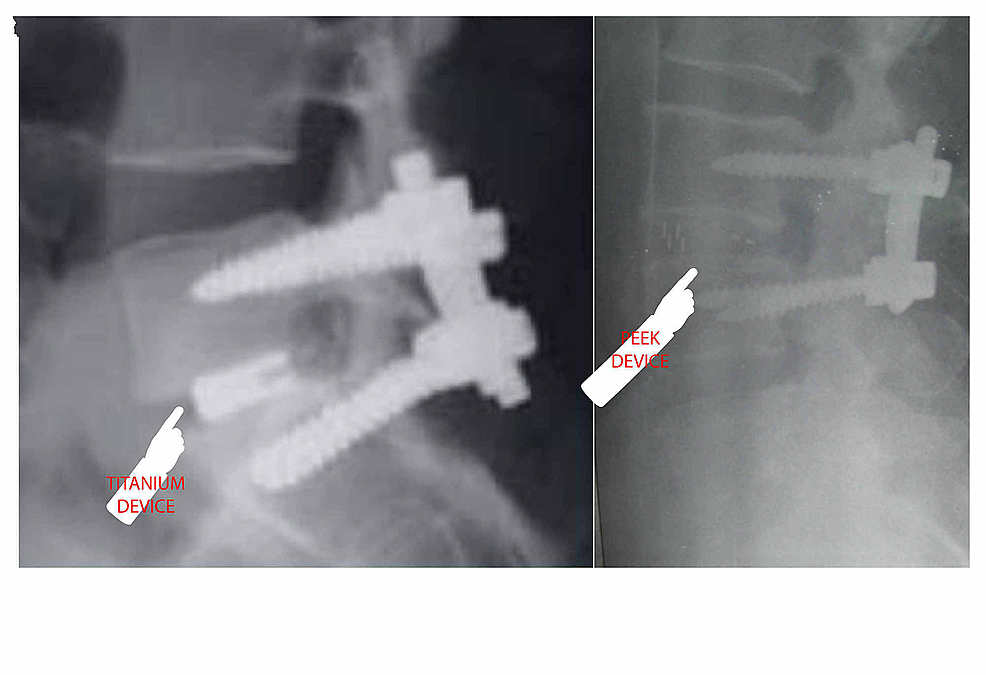

From www.researchgate.net